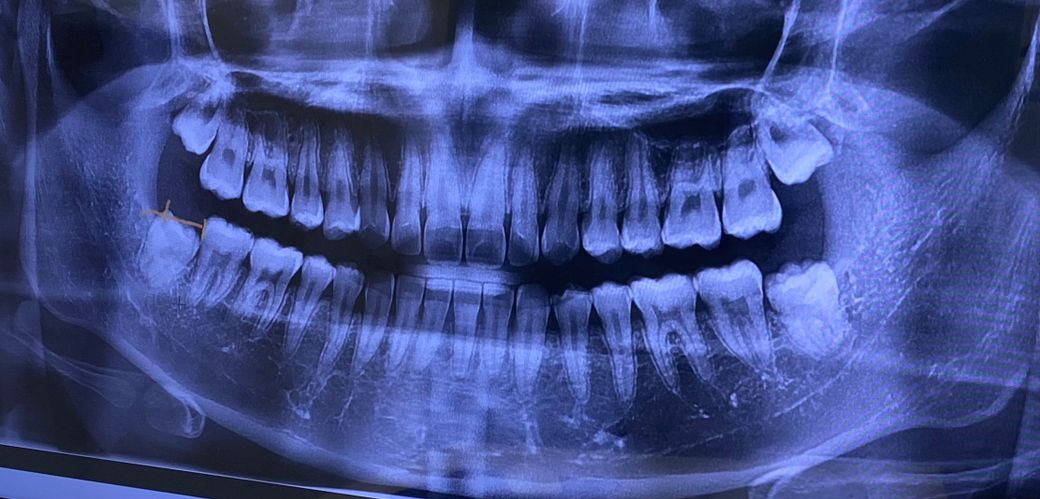

엑스레이 찍었는데 충치있는걸까요?

이가 시려소 사랑니때문인가 하고 사랑니 전문치과를 갔는데 꼭 그것때문만은 아닌것 같아서요 침삼킬때 어금니 부분이 시립니다 혹시 충치때문인지 충치가 있는건지 궁금합니다

충치떄문에 시릴꺼 같진 않고 잇몸이 안좋거나 치경부 마모증때문에 그럴 가능성이 있습니다.

이가 시려소 사랑니때문인가 하고 사랑니 전문치과를 갔는데 꼭 그것때문만은 아닌것 같아서요 침삼킬때 어금니 부분이 시립니다 혹시 충치때문인지 충치가 있는건지 궁금합니다 -> 사랑니 옆 어금니에 충치가 있어보이진 않습니다